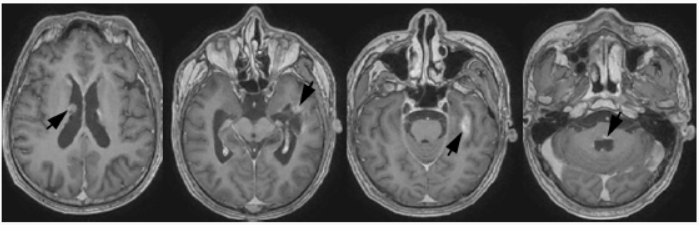

影像学检查:头部MRI检查(2015年8月14日)显示,左侧颞叶和脑室系统弥漫性异常信号结节,体积较大者位于左侧颞叶,约4.40 cm×3.70 cm,考虑为多发性脑膜转移瘤伴脑转移瘤(图1)。

图1首次放射治疗前头部MRI检查所见(2015年8月14日)1a横断面增强T1WI显示,双侧侧脑室旁弥漫性脑膜转移灶,呈局部强化征象(箭头所示)1b横断面增强T1WI显示,左侧颞叶和第四脑室旁大体积脑转移灶,呈局部强化征象(箭头所示) 医学百科网 | YxBaike.Com